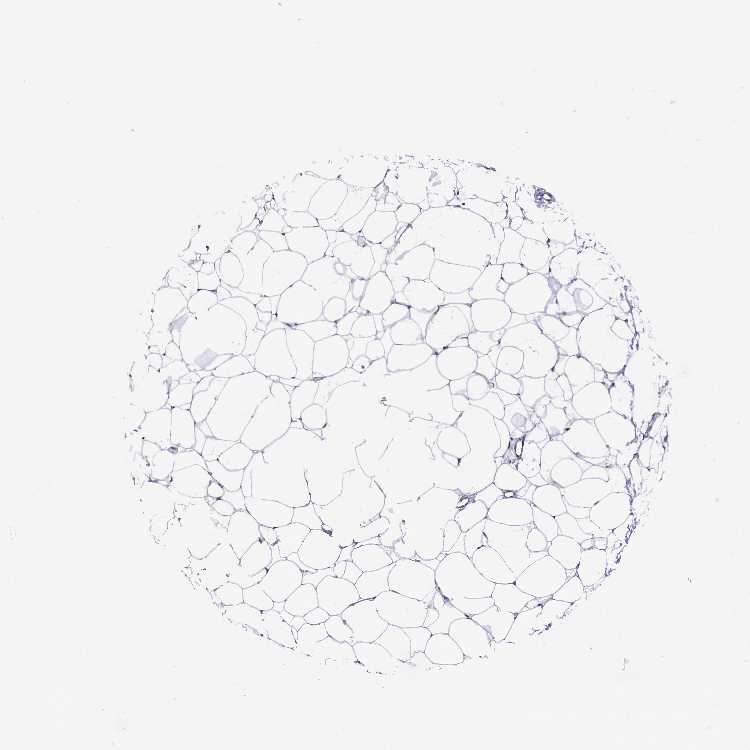

TISSUE PRIMARY DATA SOFT TISSUE Show tissue menu

SOFT TISSUE - Expression summary

SOFT TISSUE 1 - Antibody stainingi

Antibody staining in the annotated cell types in the current human tissue is reported as not detected, low, medium, or high, based on conventional immunohistochemistry profiling in selected tissues. This score is based on the combination of the staining intensity and fraction of stained cells.

Each image is clickable and will lead to virtual microscopy that enables deeper exploration of all samples and also displays staining intensity scores, fraction scores and subcellular localization as well as patient and tissue information for each sample.

Antibody HPA042139Antibody HPA058526

Chondrocytes MediumLow

Fibroblasts MediumNot detected